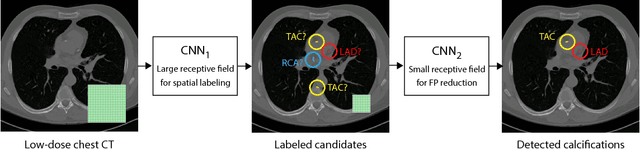

Abstract:Heavy smokers undergoing screening with low-dose chest CT are affected by cardiovascular disease as much as by lung cancer. Low-dose chest CT scans acquired in screening enable quantification of atherosclerotic calcifications and thus enable identification of subjects at increased cardiovascular risk. This paper presents a method for automatic detection of coronary artery, thoracic aorta and cardiac valve calcifications in low-dose chest CT using two consecutive convolutional neural networks. The first network identifies and labels potential calcifications according to their anatomical location and the second network identifies true calcifications among the detected candidates. This method was trained and evaluated on a set of 1744 CT scans from the National Lung Screening Trial. To determine whether any reconstruction or only images reconstructed with soft tissue filters can be used for calcification detection, we evaluated the method on soft and medium/sharp filter reconstructions separately. On soft filter reconstructions, the method achieved F1 scores of 0.89, 0.89, 0.67, and 0.55 for coronary artery, thoracic aorta, aortic valve and mitral valve calcifications, respectively. On sharp filter reconstructions, the F1 scores were 0.84, 0.81, 0.64, and 0.66, respectively. Linearly weighted kappa coefficients for risk category assignment based on per subject coronary artery calcium were 0.91 and 0.90 for soft and sharp filter reconstructions, respectively. These results demonstrate that the presented method enables reliable automatic cardiovascular risk assessment in all low-dose chest CT scans acquired for lung cancer screening.